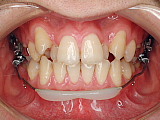

装置は歯に接着してあるだけですので、専用の器具で簡単にはずせます。

治療終了後は歯の裏側にリテーナーを装着し、年に1度くらいの定期検査を続けます。 |

歯を抜かない矯正ですべての歯を並べることができました。 |